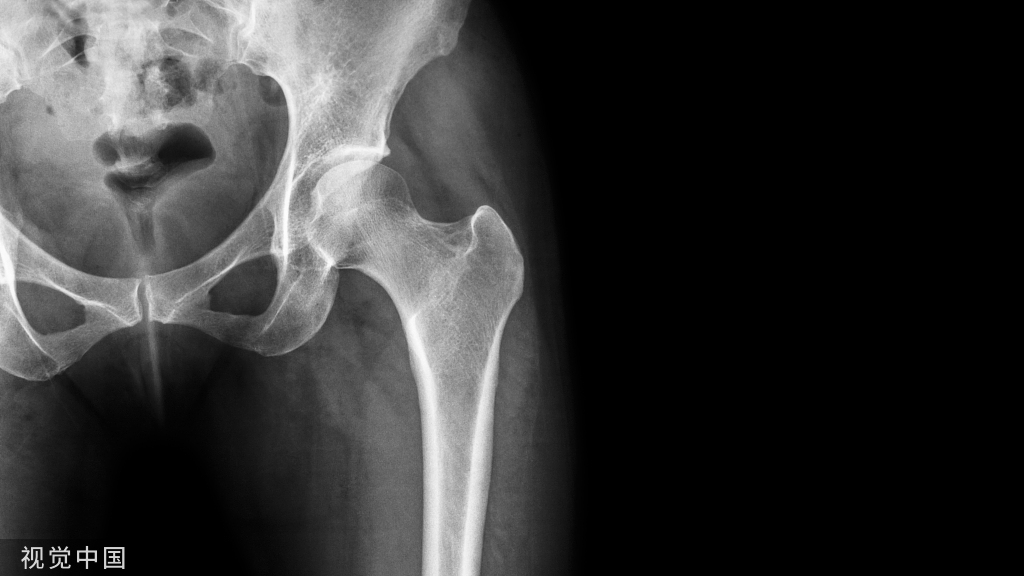

支撑作用又称抗滑动作用,通常应用于干骺端劈裂骨折,如胫骨平台、踝关节等,以抵抗轴向劈裂或剪切力。

特别是对干骺端骨折,如股骨近端、股骨远端、桡骨远端等,将骨折靠近关节面端用锁定螺钉将钢板与骨块固定,后利用钢板原有解剖结构,将钢板固定至另一骨折端,达到骨折复位的目的。